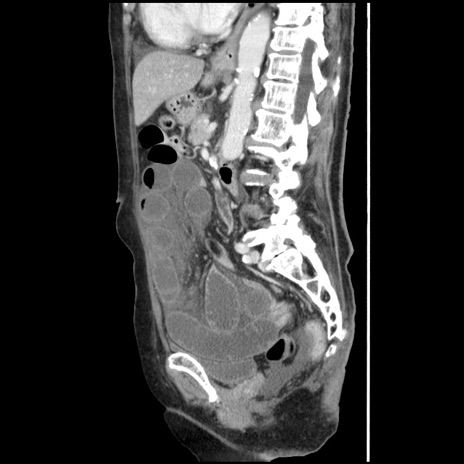

症例1(矢状断像)

【症例】80歳代女性

【主訴】腹痛

【現病歴】8時間前から腹痛あり来院。

【既往歴】糖尿病、脂質異常症、子宮体癌にて子宮全摘術

【身体所見】意識清明・会話良好だが腹痛で苦悶様、全腹部にわたって反跳痛と圧痛あり

【データ】WBC 13600、CRP 0.14、LDH 224、CK 90